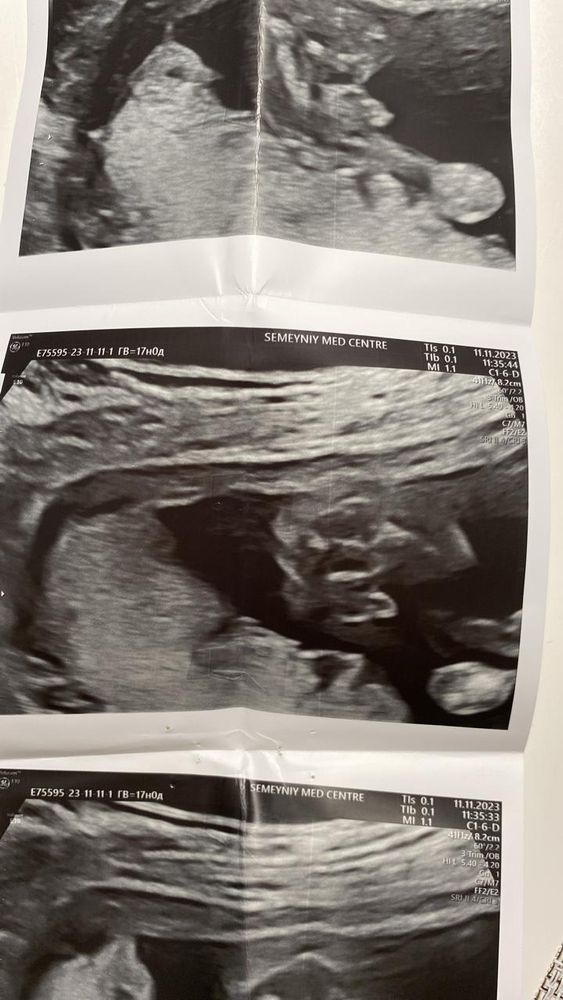

Узи мальчик

у нас было гендер - пати, и только после него открыли фото узи, у нас мальчик , но сколько бы я не разглядывала фото , не могу понять где увидели то самое мужское достоинство 🤭

Опытные, помогите понять🙏🏼

Вот же)))